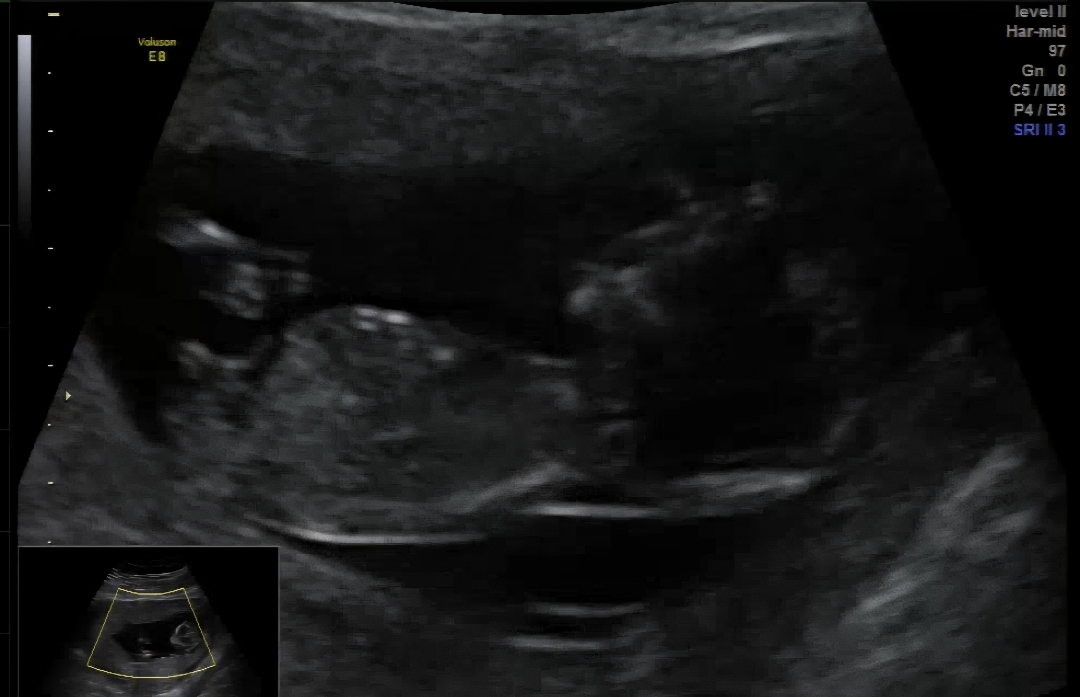

성별 뭐같나요?

12주1일입니당 지나가시면서 투표 한번 해주세요